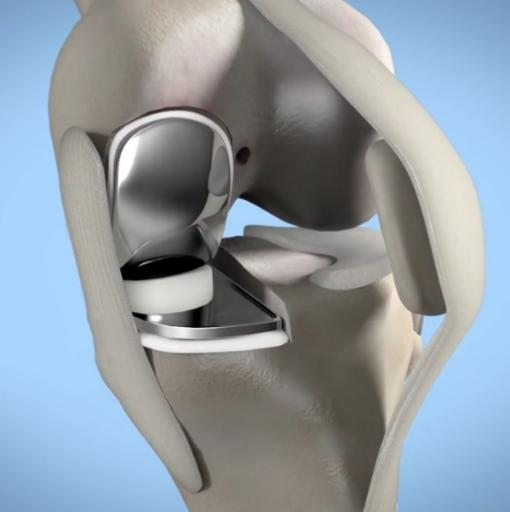

3d演示——膝关节单髁置换术_膝关节置换术

膝关节内侧单髁置换